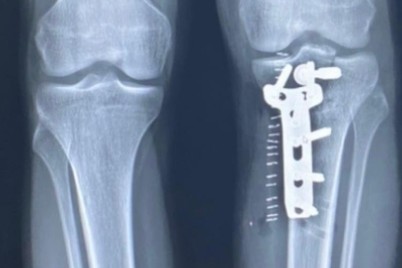

عسير - عبدالرحمن الزهراني تمكن فريق طبي بمستشفى أبها الخاص العالمي برئاسة استشاري جراحة العظام الدكتور محمد لافي العتيبي...